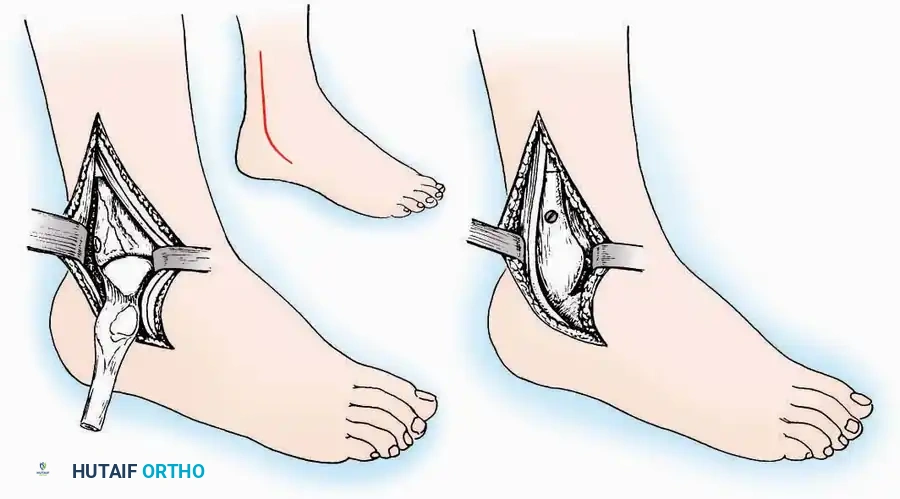

Anterior Approach

Indications: Total ankle arthroplasty (TAA), anterior ankle arthrodesis, and excision of anterior tibial/talar osteophytes (anterior impingement).

Surgical Technique:

* Incision: Make a 10 to 15 cm longitudinal incision over the anterior aspect of the ankle, centered exactly midway between the medial and lateral malleoli.

* Superficial Dissection: Incise the superficial fascia. Identify and protect the superficial peroneal nerve branches laterally and the saphenous nerve medially.

* Internervous Plane: The deep dissection exploits the plane between the Extensor Hallucis Longus (EHL) tendon (innervated by the deep peroneal nerve) and the Extensor Digitorum Longus (EDL) tendons (also innervated by the deep peroneal nerve).

* Neurovascular Bundle: Incise the extensor retinaculum. Carefully identify the anterior tibial artery and the deep peroneal nerve, which typically lie between the EHL and EDL, or directly deep to the EHL. Retract the neurovascular bundle laterally with the EDL, or medially with the EHL, depending on the specific anatomical variant encountered (lateral retraction is most common).

* Capsulotomy: Incise the anterior joint capsule longitudinally. Elevate the capsule subperiosteally from the anterior tibia and the talar neck to expose the entire tibiotalar articulation.